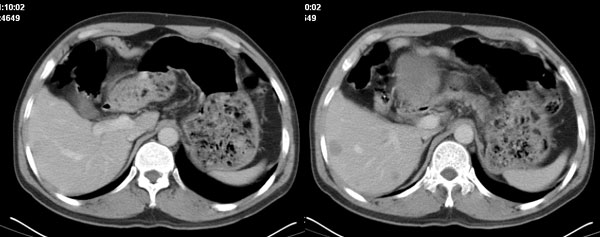

影像学表现:1 腹腔前中部、胰腺前方囊实性病灶(个人认为确定有否实性成分存在这是关键,涉及到鉴别诊断,如果是口服阳性造影剂则可明确左侧是不是小肠了),囊性部分囊壁不均,实性部分有强化,与小肠关系较密切,局部小肠受推移;与胰头、胃后壁均有脂肪间隙存在;2 胰腺无异常改变,胰周无渗出;3肝后段包膜下2个小圆形低密度灶,从图像和楼主提供的ct值来看有轻度强化,灶周无片状强化,不似单纯囊肿及肝癌、炎性病变表现;4 腹膜后及腹腔内无淋巴结肿大。

分析:1 如果腹腔内是囊实性病灶,则应多考虑肿瘤性病变,如源于小肠的间叶源性组织如神经源性肿瘤或间质瘤等;如果这么大存在恶性变的可能,那么肝内则可考虑为转移,征象亦符合;这种可能性最大;

胰腺边界清晰,胰周筋膜不厚,胰周脂肪密度无明显增高;其前方囊实性病灶,边界清晰,增强后实性部分轻度强化;肝内多发边界清晰低密度影,增强后无明显强化(平扫ct值42.9,动脉期48.6,静脉期58.2,延迟期62.2)。

原因:胰头前方,前上腹部巨大囊实性肿物,与小肠关系密切,与胰头及胃壁之间脂肪间隙存在,囊壁不均匀,部分强化,占位效应明显,小肠上段扩张,十二指肠及胃腔内大量食物存留,说明上消化道有部分梗阻。因此,考虑来源于肠道的肿瘤。再结合其病史及肝内改变,这样考虑更有道理。

同意腹腔内囊实性恶性肿物伴肝内转移。